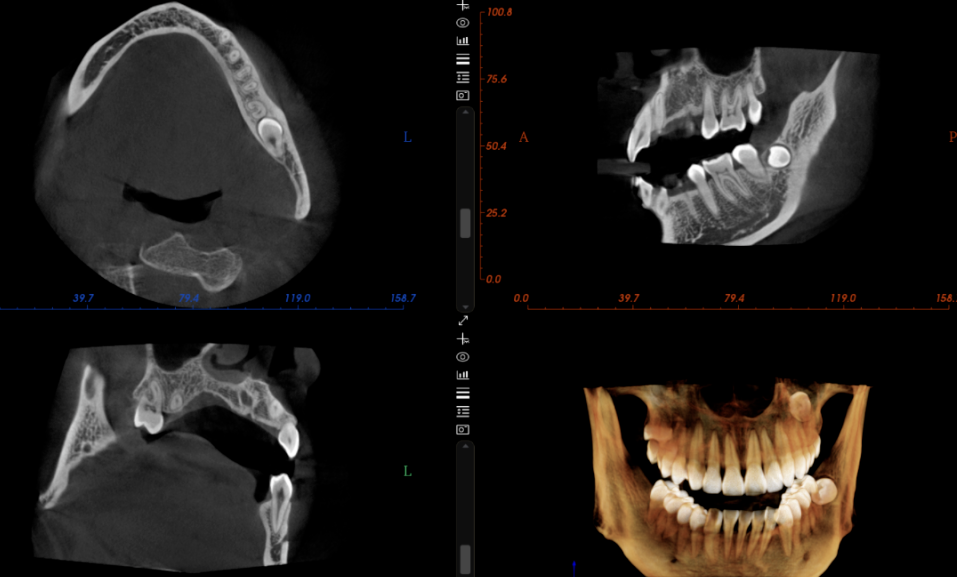

因為CT技術解決了傳統口腔X射線設備如口內牙片機和全景機所存在的圖像重疊和畸變問題。通過360°全方位立體觀測牙床的骨密度、牙槽骨的高度和寬度等數據,不僅可以完整重建顱面區域的結構,還能夠精確測量頜面骨骼結構,並還原細緻的解剖細節。

種植牙醫生可以借助CT機精確判斷全口牙床的位置、牙槽骨的高度和深度等資訊。這使得醫生能夠在電腦上清晰地分析牙槽骨的狀態,並在電腦上預先規劃種植手術,選擇適當的種植體,確定最佳的種植位置和角度。這進一步幫助醫生製作精准的手術範本,從而使種植牙手術更加安全可靠。